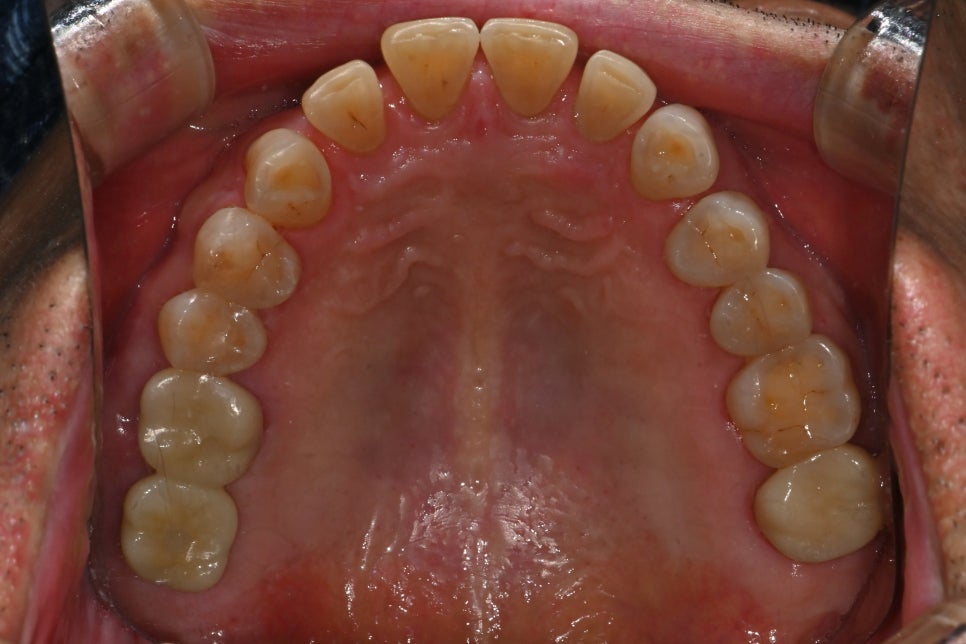

The final stage of an implant is the prosthesis (crown).

It is the stage where the visible tooth shape is completed, but in reality, it involves some of the most delicate work.

Fit between the gums and the prosthesis

Harmony of height and width with the surrounding teeth

Adjustment of the prosthesis shape according to the chewing direction

This patient tended to have a bite that leaned to one side, so in the prosthetic stage of the implant treatment, we designed it to distribute that force as much as possible.

It was custom-made at the in-house dental lab based on scan data, and after placement, photographs were used to check the fit between the gums and the prosthesis again.